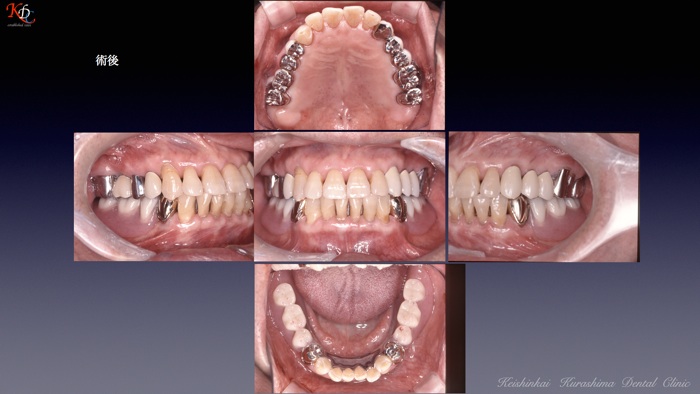

治 療例 1